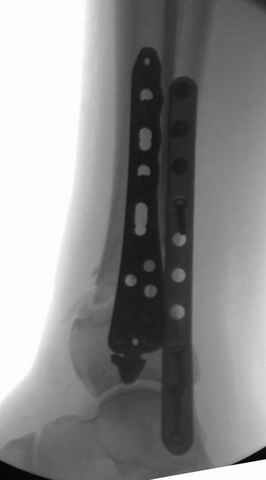

Фиксация переломов малоберцовой: пластина, интрамедуллярные конструкции или tension band technique.

Если перелом низкий и поперечный, делаю интрамедуллярно, спицей или интрамедуллярным штифтом, при косых переломах пластина (antiglide technique), при пользовании аппарата Илизарова спицу провожу через тибиа-фибула.

На снимках варианты фиксации малоберцовой:

№ 1 двух лодыжек